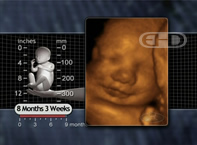

• Baby's foot is now about three inches long (about 7½ cm). • Baby sometimes drinks 450cc (or 15 oz) of amniotic fluid each day. • Air breathing begins. | |